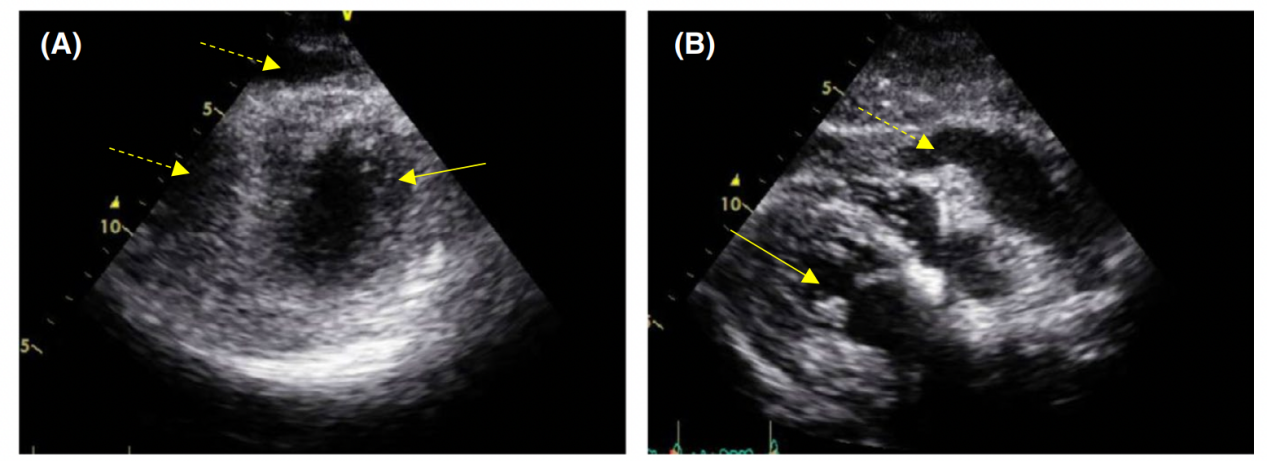

根据病人的血压,没有强烈怀疑休克状态和脑血管疾病。然而,超声心动图显示右心室压力增加和心包积液(图1)。患者自诉背部疼痛不强烈但持续,并有短暂的神经系统症状记录;因此怀疑主动脉夹层。

图1: 超声心动图在入学。A,左室短轴图像显示因心脏填塞导致右心室充盈受损。B,左心室长轴图像显示大量心包积液。←,表示左心室;⇠,显示心包积液